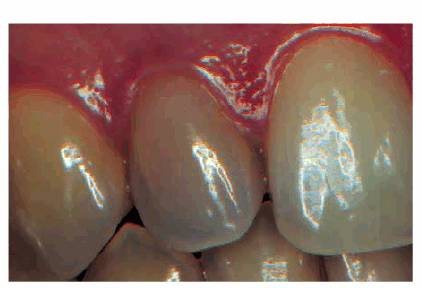

hue would more than likely indicate internal hemorrhage from a recent injury (Figure 19-2), a dental procedure (Figure 19-3), or gingival tissue hyperplasia

Figure 19-3: One week following crown preparation, the tooth structure was red, signifying extravasation of blood and the need for pulp extirpation.

Figure 19-4A: Pink spot as a result of external resorption.

Figure 19-33A: Pink crown preparation 1 week following instrumentation.